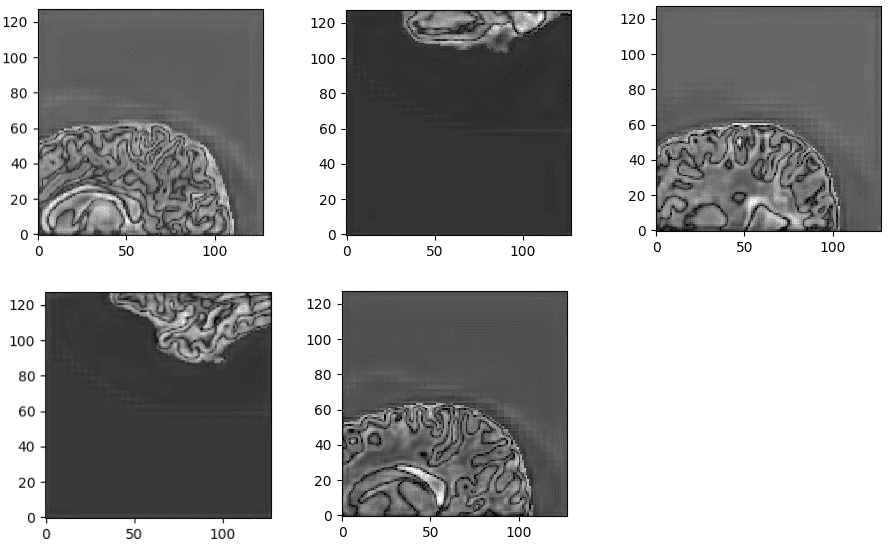

该模型在子卷的验证集中达到了大约 93% 的骰子系数分数。最后但同样重要的是,让我们看看验证集中 3D-Unet 的一些可视化预测。尽管预测是 3D 体积,但我们在这里只展示一个代表性切片。通过获取 MRI 的多个子体积,可以将它们组合起来形成完整的 3D MRI 分割。请注意,我们使用子卷采样的事实是数据增强。

来自训练有素的 3D-Unet 的非标准化最后一层预激活。网络学习高度语义的任务相关内容,这些内容对应于类似于输入的大脑结构。

我们的预测 VS 基本事实。您认为哪个预测是基本事实?仔细看看再做决定!需要注意的是,我们在这里只展示了中轴切片,但预测是一个 3D 体积。可以观察到,该网络完美地预测了空气体素,但难以区分组织边界。但是,让我们再次检查以找出真正的那个!

现在,我相信您可以区分基本事实。如果不确定,请查看文章末尾:)